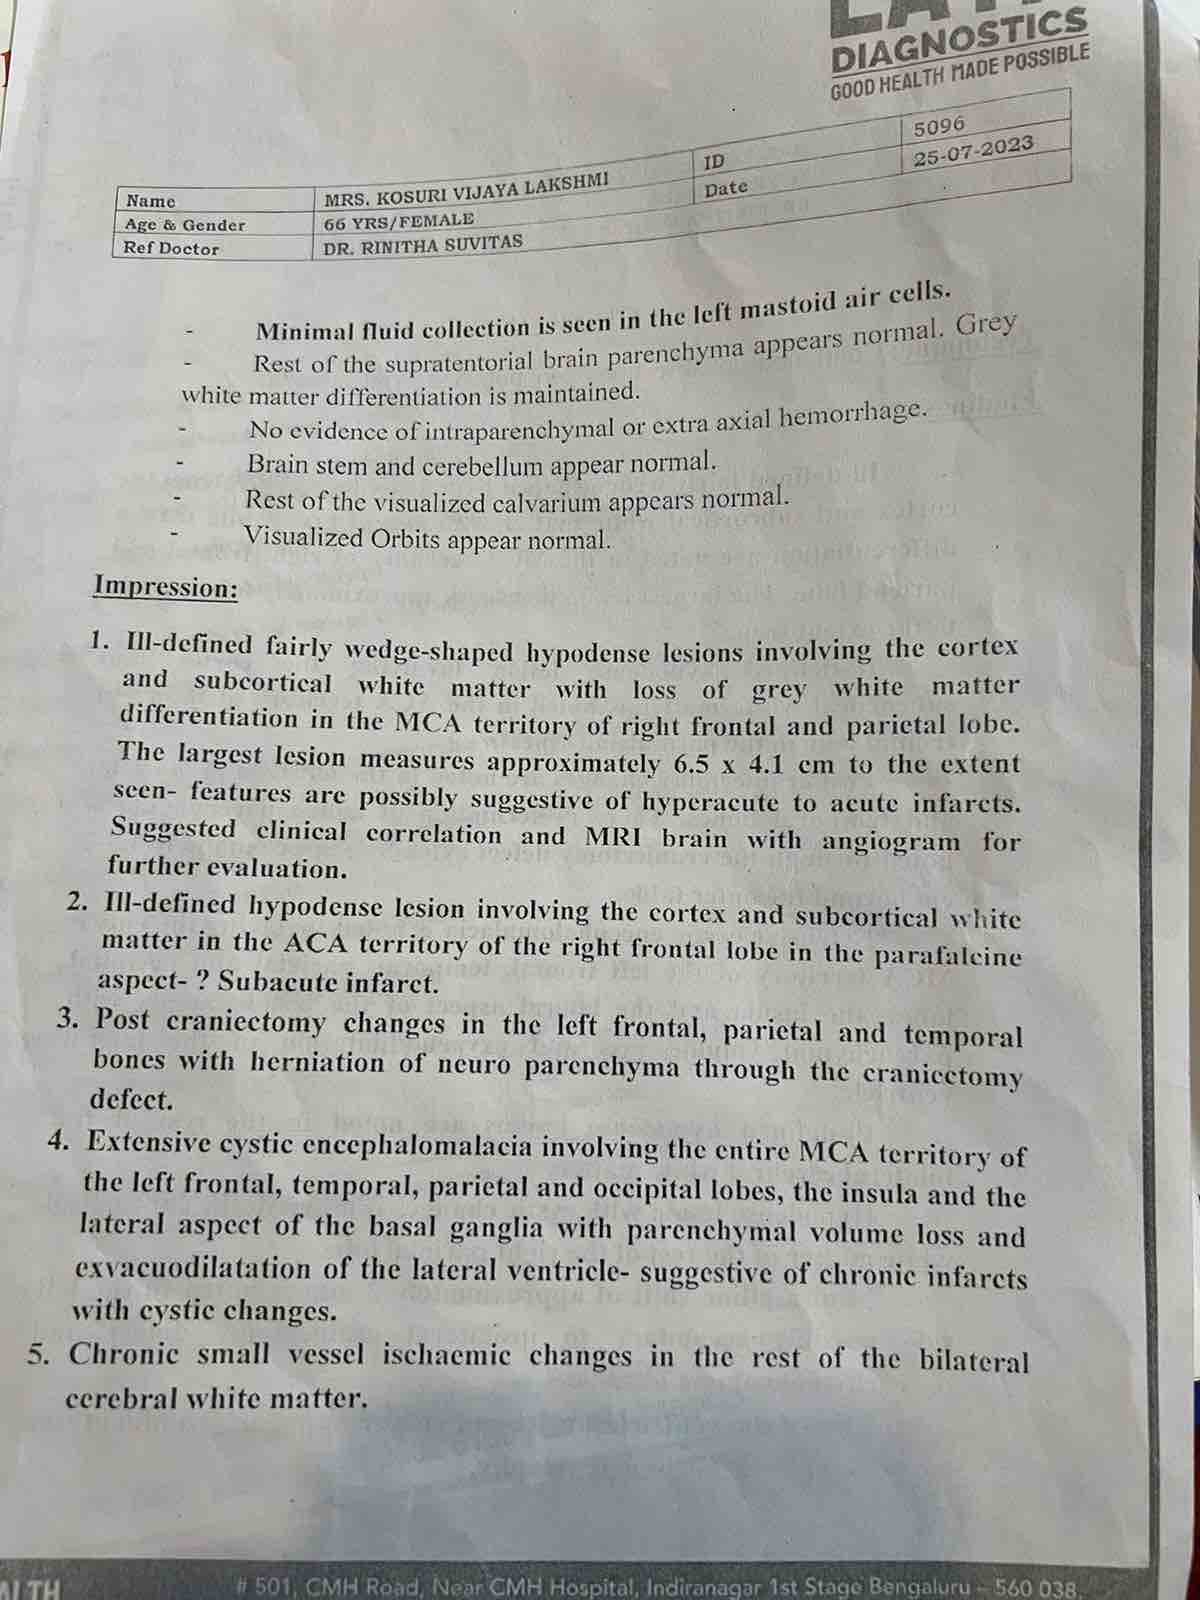

We are reaching out to you today with a heavy heart and a plea for help. Our beloved 66-year-old mother K VIJYA LAKSHMI, has been facing an incredibly challenging journey since 16th May when she had brain stroke & underwent emergency brain and abdomen surgery. Her recovery has been a rollercoaster of ups and downs.

During her hospitalization, she endured multiple complications, including respiratory distress, recurrent severe infections, and even seizure-like activity. Through it all, she has shown immense strength and determination. Still she require three more surgeries to stand on the path of recovery.